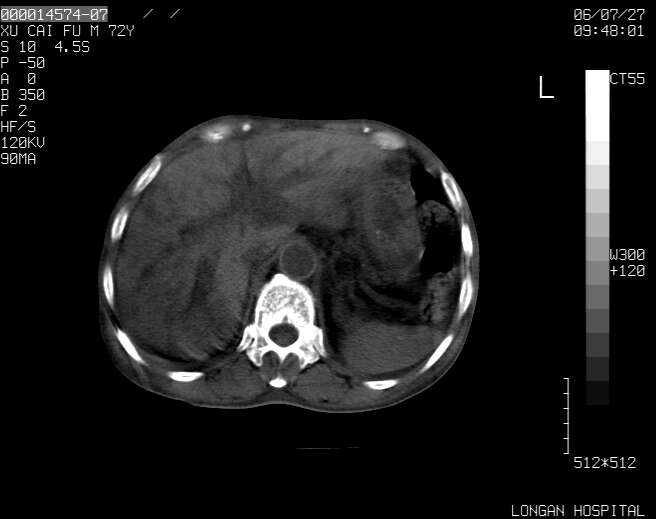

以下是引用winter在2006-7-30 20:14:00的发言:[br]1、考虑胆囊癌伴胆道侵犯并高位胆道梗阻、肝内多发转移、腹膜后淋巴结转移。[br]2、右肾轻度积水。[br]3、老人家72岁了胰腺头体尾部均较饱满,不过未见密度异常及其他异常征象。[br]4、腹水。

以下是引用jiajie在2006-7-31 7:10:00的发言:[br]考虑肝转移瘤,腹膜后淋巴结增大。[br]胃癌不能除外,建议胃镜检查。